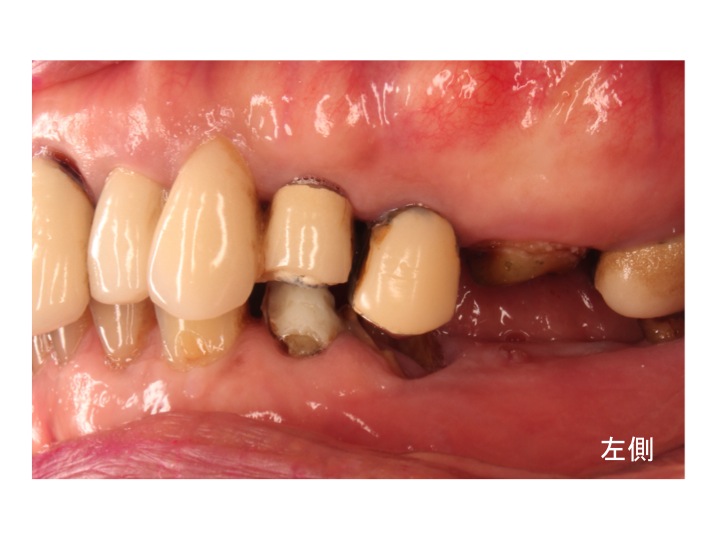

エムドゲイン(EMDOGAINTM®)は、歯周組織再生誘導材料と言われるものです。

スウェーデンのビオラ社で開発された歯周組織再生誘導材料です。

エムドゲインの主成分は子供の頃、歯が生えてくる時に重要な働きをするたんぱく質の一種です。

このエムドゲインをルートプレーニングを行い、汚染組織を除去した後、

歯の根に塗ることにより、歯の発生過程に似た環境を再現します。

その結果、骨や歯肉繊維を再生させるのです。